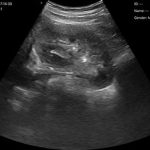

El escáner de ultrasonido portátil de doble sonda es una solución avanzada diseñada para ofrecer máxima versatilidad clínica en un solo dispositivo. Gracias a su tecnología integrada, combina tres modos de escaneo —convexo, lineal y phased array— permitiendo evaluar estructuras profundas, tejidos superficiales y realizar estudios cardíacos con alta precisión. Esta integración reduce significativamente los costos al reemplazar la necesidad de adquirir múltiples sondas por separado.

| Ángulo/longitud de escaneo | Convexo 60, Lineal 40 mm |

| Frecuencia | Sonda convexa de 3,5/5,0 MHz, sonda lineal de 7,5/10 MHz |

| Profundidad de la pantalla | Convexo 90 ~ 305 mm, Lineal 20 ~ 100 mm |

Abdomen

Cardíaco

Pulmonar

Obstetricia